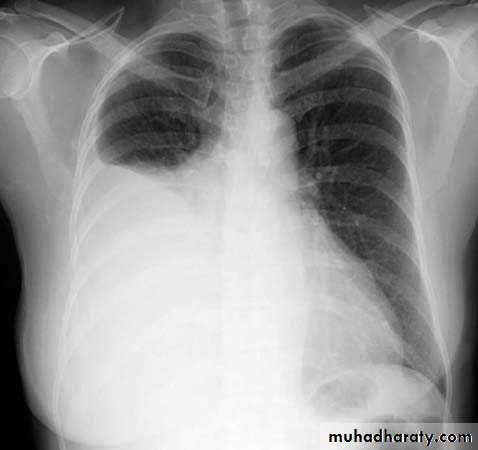

What is the main difference between 2 films ??? What is the shape of each one ??? A. B.

44.A.RT middle lobe consolidation

B.RT middle lobe collapse

Miliary TB